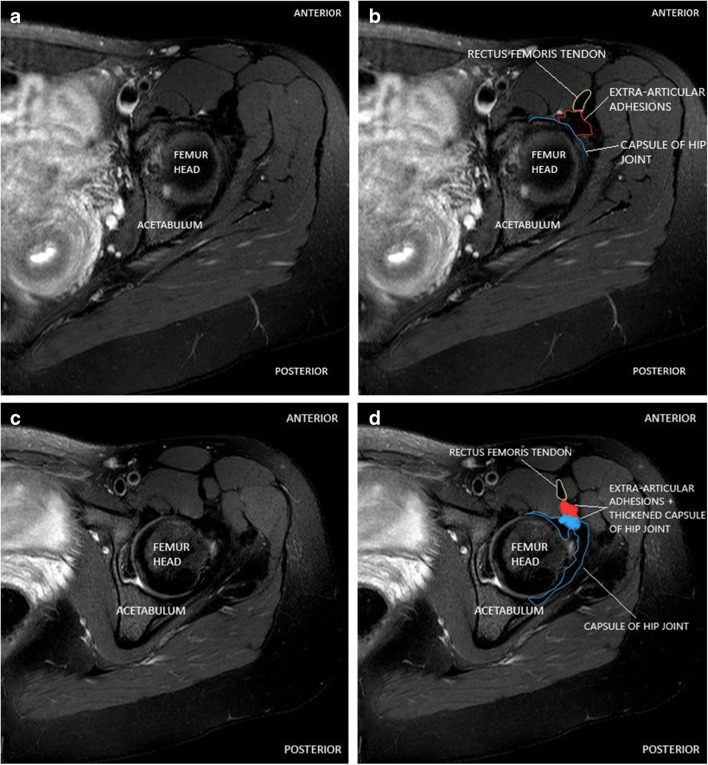

Fig. 4.

Axial T2 fat saturated MRI image hip in a 27-year-old female patient demonstrating rectus femoris tendon (outlined by yellow line), capsule of hip joint (outlined by blue line), and extra-articular adhesions (outlined by red line) with loss of tissue plane (shaded blue and red areas in Fig. 4d) between these structures along the anterior portal tract of hip arthroscopy compared to preserved tissue plane at similar levels in Fig. 3a and b

Post-operative pain following surgery for femoroacetabular impingement has been attributed to formation of intra-articular adhesions, extra-articular adhesions along the scope portal, repeat injury to intra-articular structures, or incomplete correction of femoroacetabular impingement bony morphology amongst other causes [4]. The intra-articular adhesions can occur between repaired portion of labrum and adjacent overlying capsule or slightly inferiorly, between femoral neck and overlying capsule. The extra-articular adhesions can occur along the arthroscopy portal tract along the anterior hip, between the external surface of joint capsule and overlying flexor tendon sheath with resultant loss of plane of separation between these structures (Figs. 2, 3, and 4).